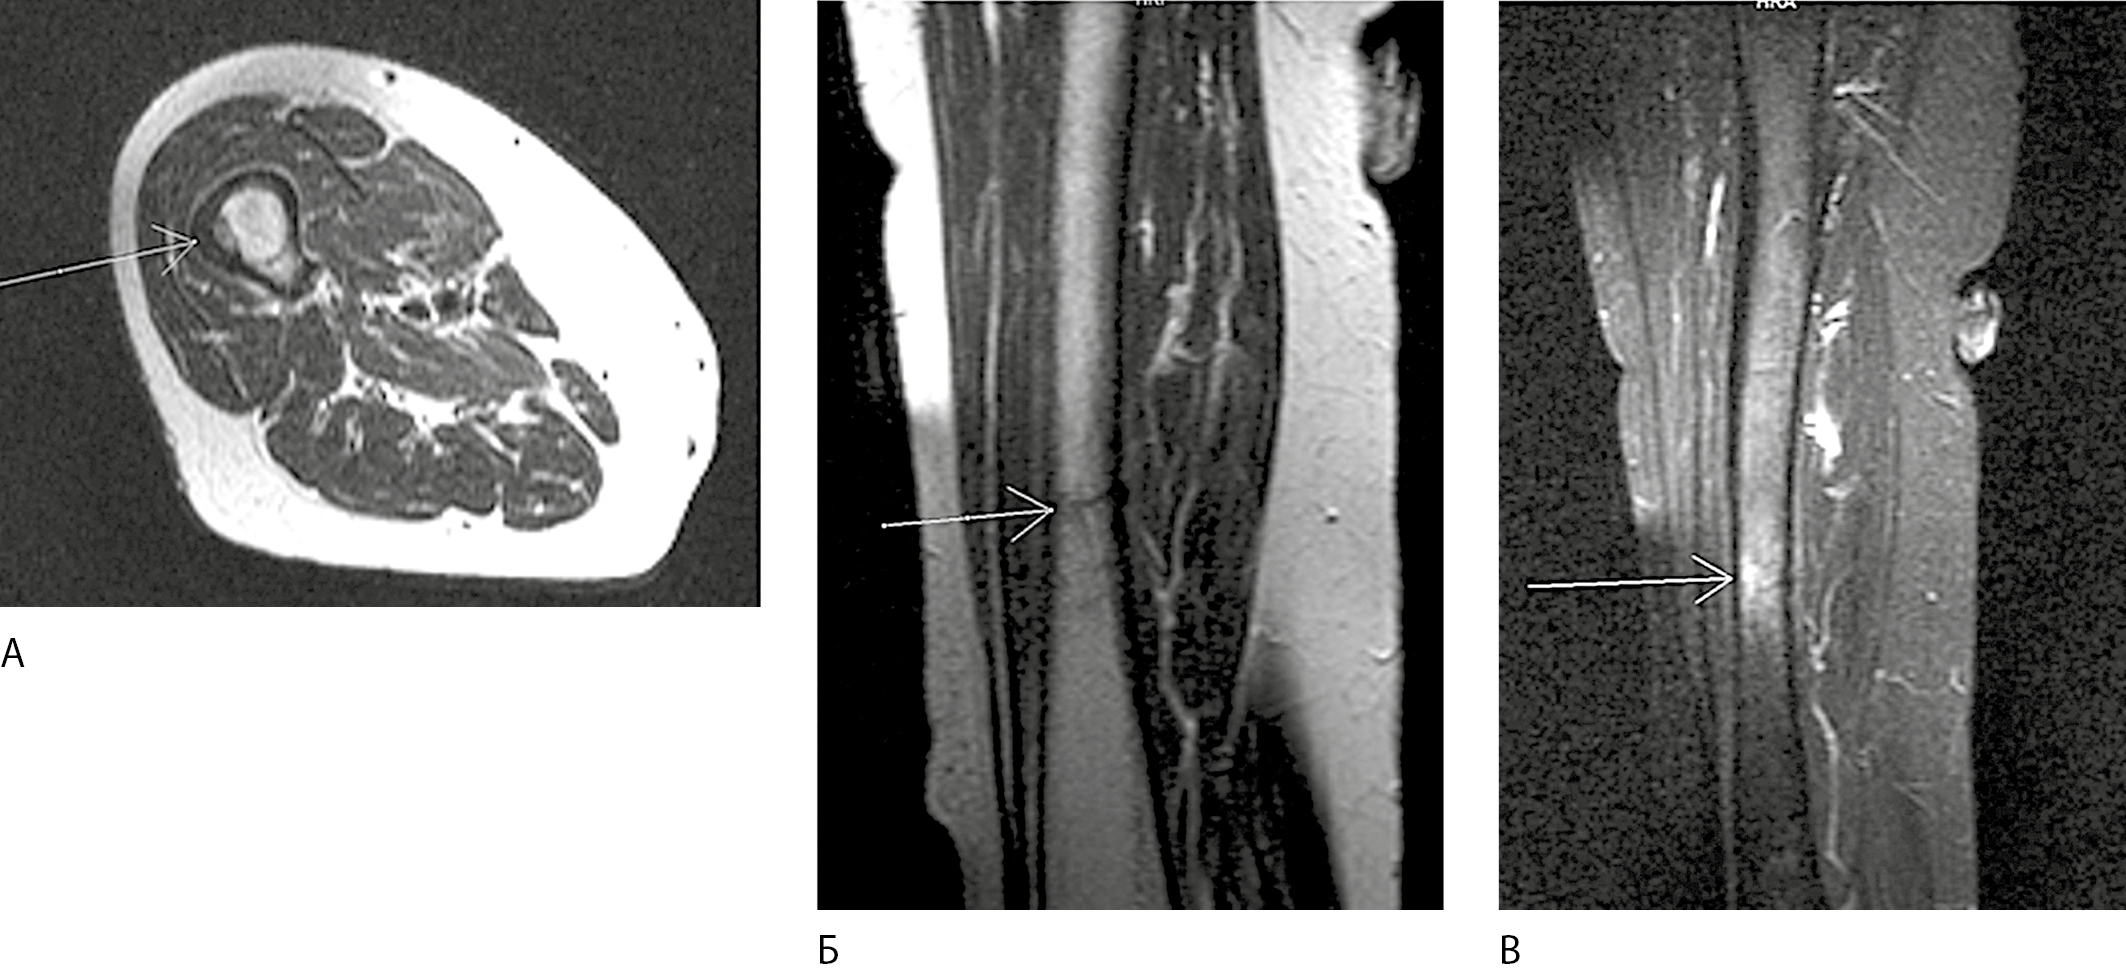

A 78-year-old woman, receiving oral bisphosphonate for severe postmenopausal osteoporosis for 3.5 years, suddenly started feeling pain in her right thigh while walking. Three months later, she had got a fracture in middle third of the right femur after falling from her standing height. According to instrumental diagnostics, this fracture had all criteria of AFF. Blocking intramedullary osteosynthesis with shafts was performed. A retrospective analysis of soft tissue magnetic resonance imaging in the area of right thigh, done before the fracture, showed the presence of undiagnosed incomplete right femur fracture in the middle third, which subsequently led to a complete fracture.

1. Fig. 1. Illustrative sections of an MRI scan of the right thigh of patient K. dated November 9, 2017 | |